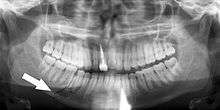

Panoramic radiographs have the capability to demonstrate a portion of the neck and display atheromas (calcifications in the carotid artery) which are an indication of both local and generalized (systemic) atherosclerosis. Atherosclerosis of the coronary arteries leading to myocardial infarction (heart attack), and atherosclerosis of the carotid artery leading to stroke are the number one and number three most common causes of death in the United States.[5]

There is interest to look at panoramic radiographs as a screening tool, however further data is needed with regards if it is able to make a meaningful difference in outcomes.[6]

Epidemiology: General Public and High Risk Groups

Additional research projects have further determined the prevalence rate of these atheromas in the general population (3-5%)[7] and among high-risk groups (over 25% in: recent stroke victims,[8] individuals with obstructive sleep apnea syndrome,[9][10] postmenopausal women,[11] type 2 diabetics,[12][13] individuals with dilated cardiomyopathy,[14] and among individuals who have received radiotherapy directed at the neck,[15][16]). These findings have been corroborated by other several other researchers.[17][18][19][20]

Atherosclerosis is attributed to risk factors that include cigarette smoking, hyperlipidemia, obesity, diabetes mellitus, and hypertension (high blood pressure). These factors, however, do not fully account for the risk of disease. Atherosclerosis has been conceptualized as a chronic inflammatory response to endothelial cell injury[21] and dysfunction possibly arising from chronic dental infection. In 2010, using the previously validated Mattila panoramic radiographic index to quantify the totality of dental infection (i.e., periapical and furcal lesions, pericoronitis sites, carious tooth roots, teeth with pulpal caries, and vertical bony defects), Friedlander’s group determined that individuals with carotid artery atheromas on their panoramic radiographs had significantly greater amounts of dental infection/inflammation than atherogenic risk-matched controls devoid of radiographic atheromas.[22][23] While the Mattila index had been previously used to relate the extent of dental infection to coronary artery disease, this research is the first to link the full range of dental disease that it measures to panoramic radiographs evidencing calcified carotid artery atherosclerosis.